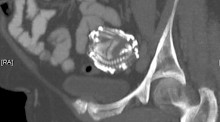

Eine ärztliche Routineuntersuchung einer 92-jährigen Chilenin hat Erstaunliches zutage gefördert: Im Körper der Frau wurde ein mindestens 50 Jahre alter mumifizierter Fötus entdeckt – ein Lithopädion oder auch Steinkind.

Die betroffene Seniorin war wegen eines Sturzes in die Klinik gebracht worden. Auf einem Röntgenbild sahen die Ärzte dann zu ihrer Verblüffung den fast zwei Kilogramm schweren Fötus. Das Ungeborene war demnach rund sieben Monate alt. Die Frau gab an, damals nichts von ihrer Schwangerschaft gewusst zu haben, und niemals Schmerzen im Unterleib verspürt zu haben.

Steinkinder entstehen, wenn ein abgestorbener Fötus einer Bauchhöhlenschwangerschaft, einer Eileiterschwangerschaft oder eines Gebärmutterrisses nicht wie üblich, vom Körper resorbiert wird, - dies geschieht üblicherweise bei Embryonen vor dem dritten Monat, - sondern durch Aufnahme von Kalk eingekapselt und mumifiziert wird. Typischerweise ist der Fötus deshalb bei Steinkindern älter als drei Monate. Da er dann schon zu groß ist, wird er nicht mehr resorbiert. Er wird vom Immunsystem der Mutter als Fremdkörper angesehen, und um ihn vor Infektionen zu schützen, wird er eingekapselt und verkalkt allmählich zum Steinkind.